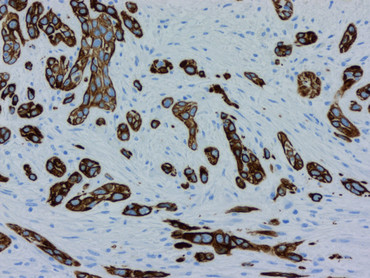

(umg) Bauchspeicheldrüsenkrebs gehört nach wie vor zu den tödlichsten Krebsarten überhaupt. In Deutschland werden dieses Jahr voraussichtlich rund 21.000 Menschen die Diagnose erhalten. Davon erliegt die Hälfte innerhalb des ersten halben Jahres der Krankheit, nur zehn Prozent überleben fünf Jahre. Neben der späten Diagnose ist eine der größten Hürden bei der Behandlung von Bauchspeicheldrüsenkrebs die erstaunliche und einzigartige Fähigkeit der Tumorzellen, sich der Behandlung zu widersetzen, indem sie ihre molekulare Identität ändern.

Der Gruppe um Johnsen ist es gelungen zu identifizieren, wie bestimmte Gene aktiviert werden, die Bauchspeicheldrüsenkrebs behandlungsresistent gegenüber Chemotherapien machen. Zunächst beobachteten die Forschenden, dass – anders als erwartet – der Zustand jener Gene, die mit der Therapieresistenz in Verbindung gebracht werden, während der Behandlung mit Chemotherapeutika unverändert bleibt. Stattdessen aktivierten bestimmte Regionen des Genoms, die bereits in therapieempfindlichen Tumorzellen aktiv waren, plötzlich neue Partnergene, die dann für die Therapieresistenz verantwortlich sind.